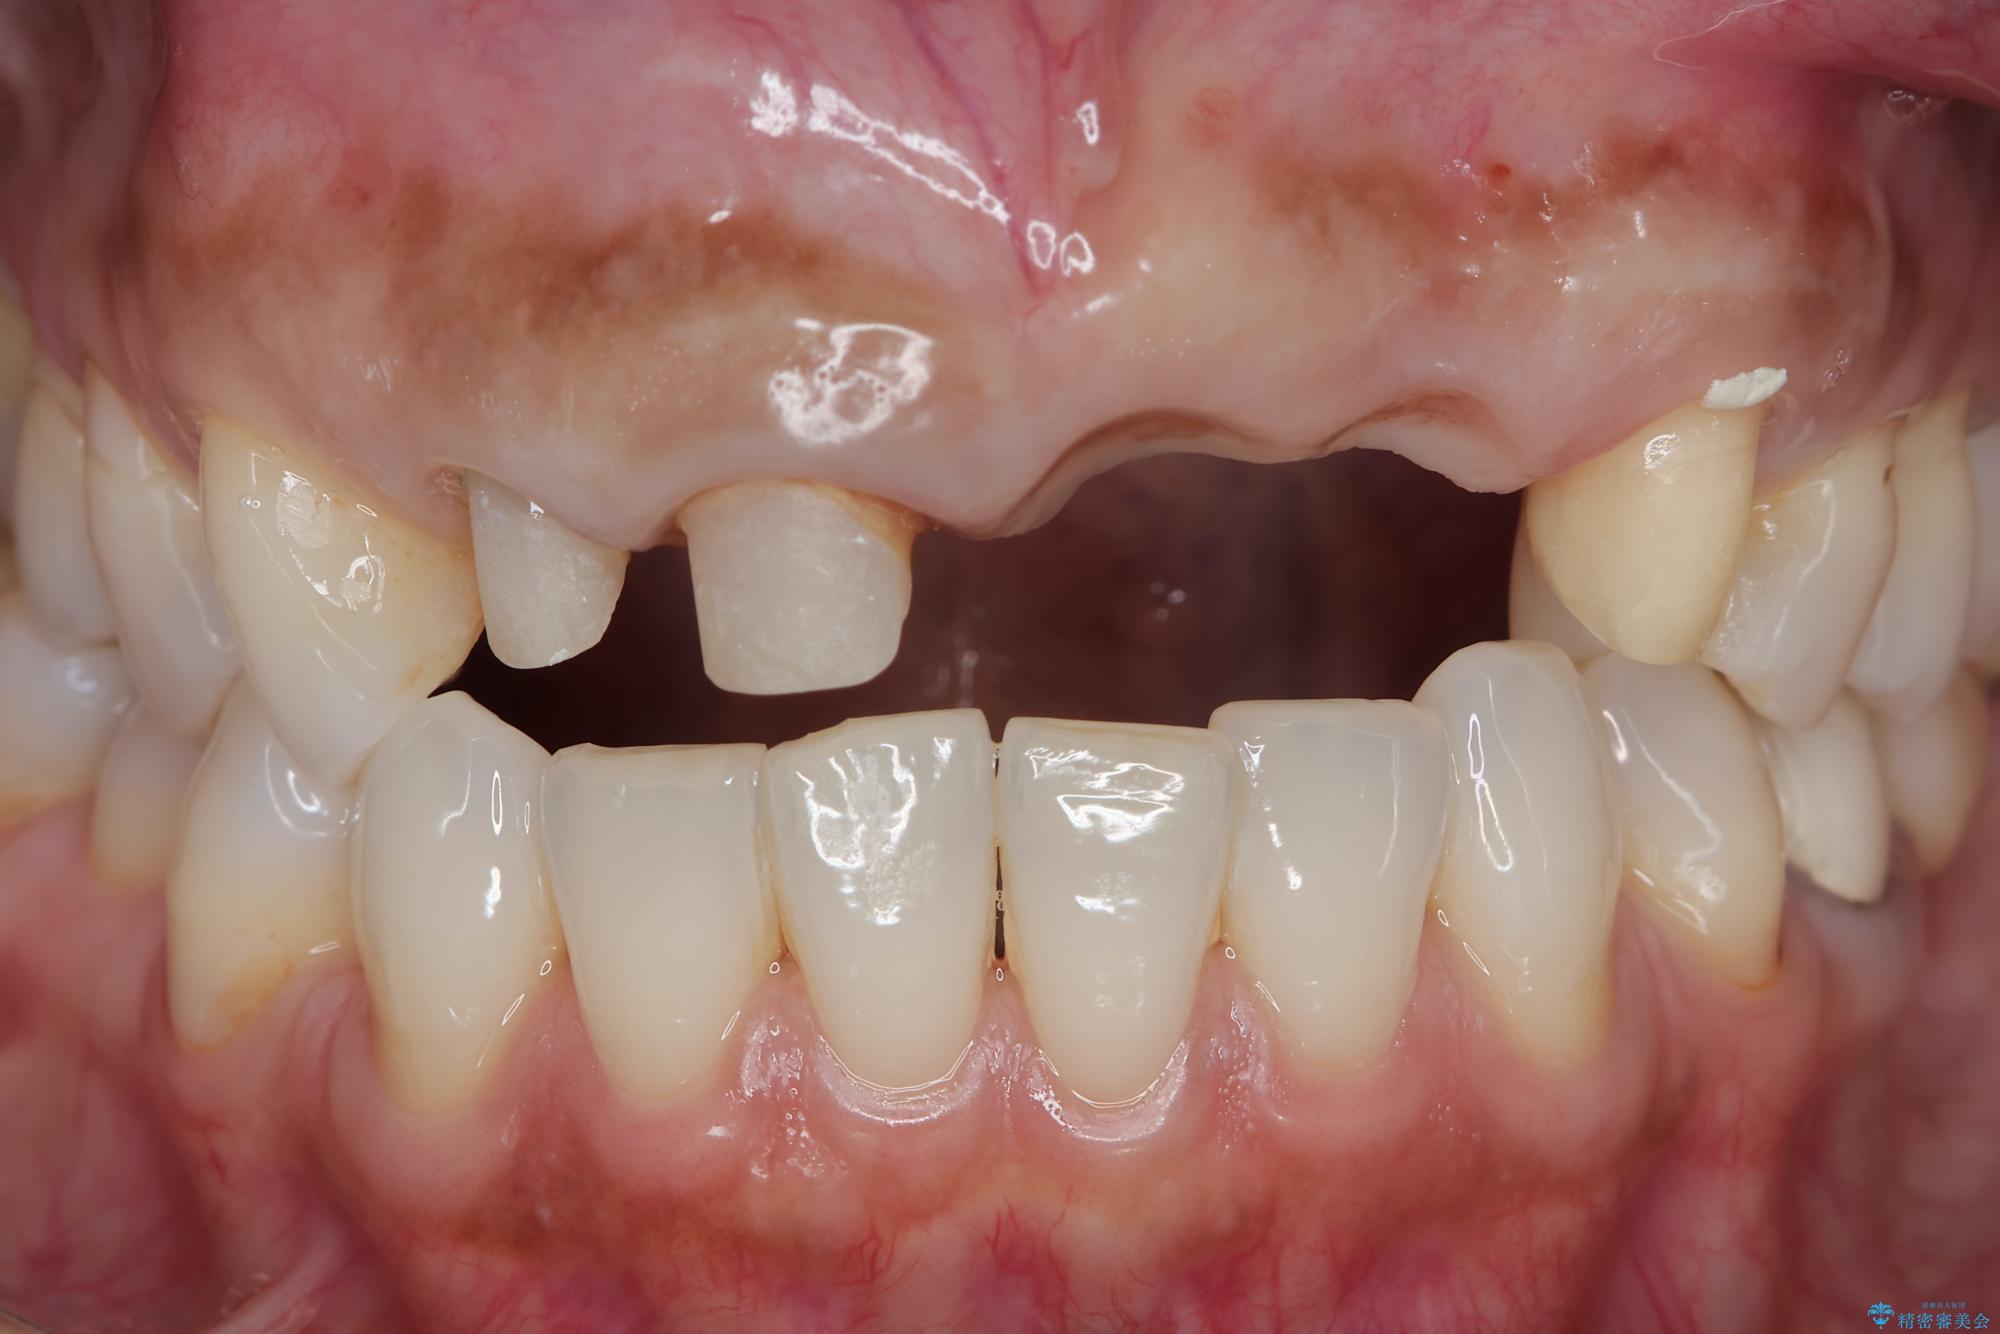

来院主訴

前歯がグラグラし、においもする、とのことで改善を求めて来院されました。

一見して問題ないように見える左側の2前歯は、セラミックを除去してみると亀裂や虫歯の再発が見られました。

治療前

歯槽堤保存術を併用したブリッジ治療 治療前画像 歯槽堤保存術を併用したブリッジ治療 治療前画像 歯槽堤保存術を併用したブリッジ治療 治療前画像 歯槽堤保存術を併用したブリッジ治療 治療前画像 歯槽堤保存術を併用したブリッジ治療 治療前画像 歯槽堤保存術を併用したブリッジ治療 治療前画像 歯槽堤保存術を併用したブリッジ治療 治療前画像 歯槽堤保存術を併用したブリッジ治療 治療前画像 歯槽堤保存術を併用したブリッジ治療 治療前画像 歯槽堤保存術を併用したブリッジ治療 治療前画像